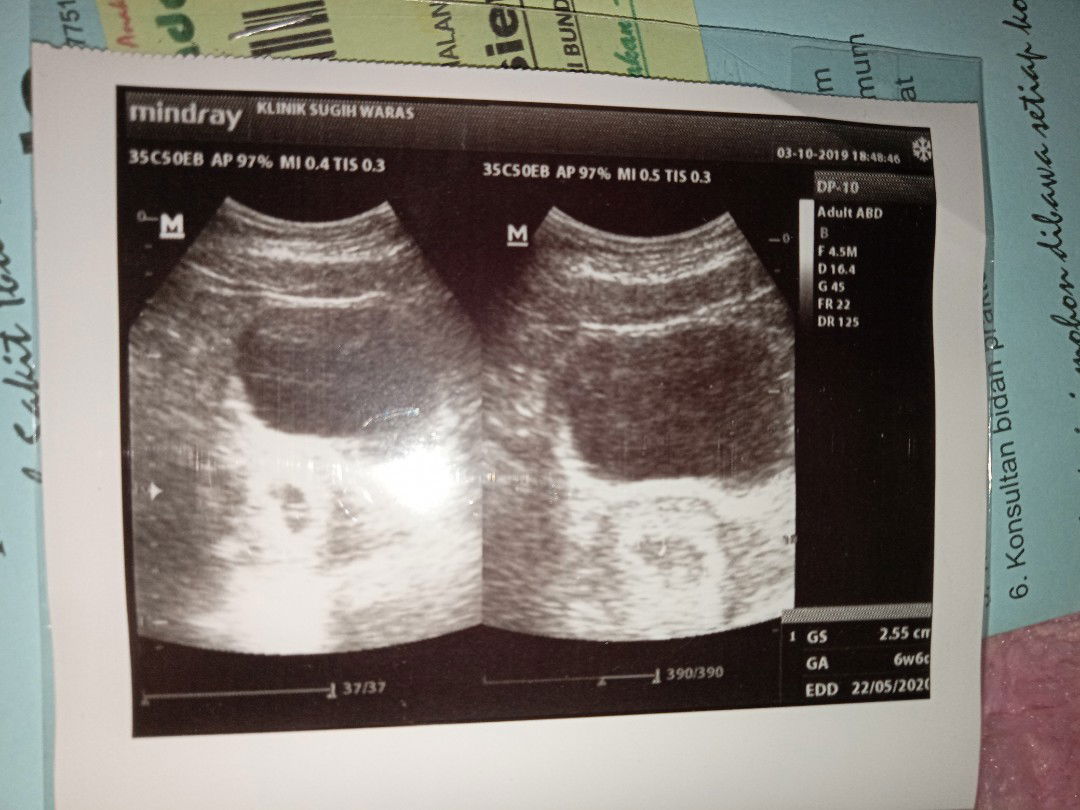

usia janin dri hasil usg

Bun mau Tanya Ini hasil usg aku tanggal 3 oktober 2019 Usia kandungannya yang mana yaa Saya bingung bun